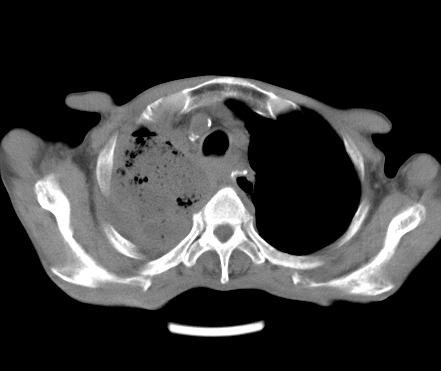

以下是引用gaoshengjiang在2008-5-30 19:53:00的发言:[br]右上叶可见大片实变影,其内可见充气支气管影及囊状影,右上叶尖端支气管走形区可见结节样影,左侧胸腔内可见胸腔胃影。纵隔淋巴结肿大。[br]考虑:1.右上肺阻塞性肺炎伴肺脓肿形成。支持转移所致。[br] 2.左侧胸腔胃。